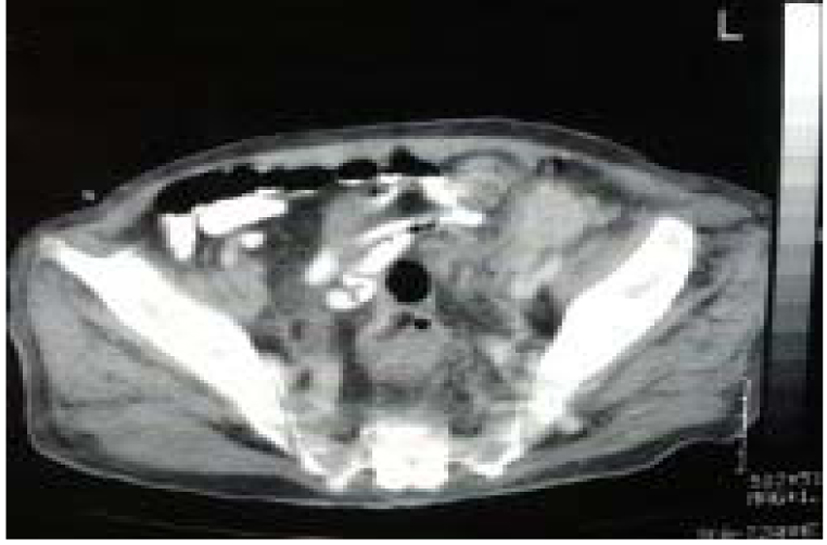

A 72-year-old patient suffering of chronic obstructive uropathy (benign prostate hypertrophy related renal insufficiency) and arterial hypertension was admitted to our hospital with anouria. His serum creatinine level was 8.5 mg/dL and his blood urea nitrogen was 387 mg/dL. He reported a long-term catheter use, for at least 5 years, because of prostatic hypertrophy and recurrent urinary retention. Physical examination revealed a palpable mass (probably corresponding to block nodes) in the left groin and an enlarged prostate gland. Abdominal ultrasound revealed excessive hydronephrosis and cortical thinning of kidneys, apparent thickening of bladder wall and a 120 cc volume prostate gland. CT of the abdomen showed a 6 cm solid mass in the left groin (Fig. 1), a small solid mass in the liver, left para-aortic and internal iliac lymph nodes and ipsilateral osteolytic lesions on the base of the pubo-ischial ramus and the pubic body. The bladder wall was thickened and the middle lobe of the prostate protruded in the lumen of the bladder. CT of the chest found no abnormalities. The patient’s renal function was improved after five dialysis sessions and bilateral placement of percutaneous nephrostomy tubes. He underwent transdermal biopsy of the mass. Histological examination diagnosed SCC of unknown origin (Fig. 2). Patient subsequently underwent additional tests. Urine cytology diagnosed uroepithelial atypia while cystoscopy revealed an ulcerated area on the left lateral wall above the ipsilateral vesicoureteral junction. Histologic examination of the TUR-BT specimens confirmed the diagnosis of stage II SR.

![]() Click for large image | Figure 1. Computed tomography (CT) of the abdomen showed a 6 cm solid mass in the left groin. |